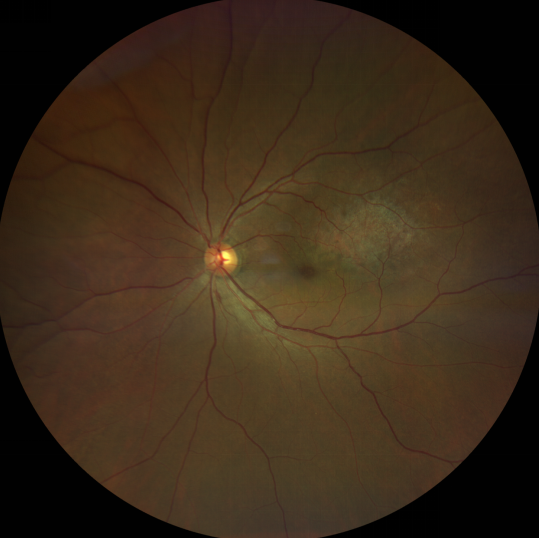

脈絡(luò)膜黑色素瘤患者在發(fā)病早期無(wú)眼痛等癥狀,當(dāng)腫瘤較小時(shí)較難發(fā)現(xiàn),隨著病程進(jìn)展,腫瘤增大,發(fā)生滲出性視網(wǎng)膜脫離或累及黃斑,視力下降才就診。

脈絡(luò)膜黑色素瘤惡性程度高,50%的患者會(huì)發(fā)生轉(zhuǎn)移,轉(zhuǎn)移到肝、肺等遠(yuǎn)處臟器,常見的轉(zhuǎn)移方式是經(jīng)鞏膜導(dǎo)管擴(kuò)散,經(jīng)視神經(jīng)蔓延者罕見。一旦發(fā)生轉(zhuǎn)移,1年生存率只有10%,即絕大多數(shù)病人在半年至1年間會(huì)失去生命。因此,早期診斷和選擇合適的治療方式對(duì)有效提高局部腫瘤的控制率、降低腫瘤的遠(yuǎn)處轉(zhuǎn)移率、延長(zhǎng)患者的生存率具有重要意義。